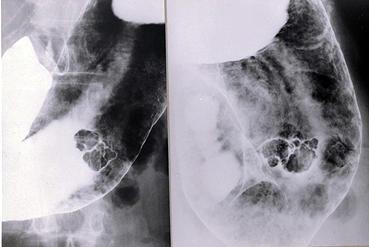

Criteria of Hist.ClassificationMalignant epithelial tumor/Adenocarcinoma

LocationStomach/Body

Technique, MethodX-ray

Macroscopic TypesType 1 Protuberant (polypoed) type/

Size35 - 40

Depth of Tumor Invasionsubmucosa